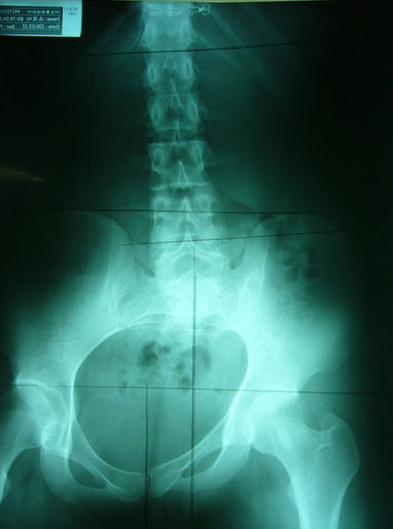

一般最常见到骨盆歪斜的案例包括产后骨盆不正、车祸、撞击、跌倒、姿势不良…等等造成。骨盆歪斜的典型症状包括腰部、髋臀部、腿、膝部疼痛。列举三个自在美国取得脊医执照以来曾经处理过骨盆歪斜相当明显的案例。都是骨盆部位曾经遭受撞击。案例A是超过十年以上的陈年车祸旧伤、另一案例B是急性摔伤(两天内)的案例。两者的X光片都依照美国脊医X摄影方式采站姿摄影评价。借此同时评价骨盆在重力(gravity)影响下的反应。也可以泯除躺歪斜摄影而造成图像不正的情况。最简单的评价要点包括骨盆高低边?中线是否穿越耻骨联合?左右两边是否对称?我简单的几条线一画,相信连外行人也可以看出明显的骨盆歪斜的情况。案例A属陈旧性伤害在调理约两个月后明显降低腰臀腿部的不舒服。而案例B属急性伤害,案例B在调理近三周后骨盆疼痛由原先的持续疼痛降低为完全不痛。之后的骨盆X光摄影重新评价也显示骨盆旋转的问题大幅改善。

案例B:左图调理前骨盆严重歪斜左右极不对称 ;右图调理后骨盆歪斜改善骨盆圈呈现对称心型圆弧

理想骨盆相对位置:两边骨盆、股骨头对称等高、中线穿过腰椎荐椎与耻骨联合、骨盆环呈现对称心形